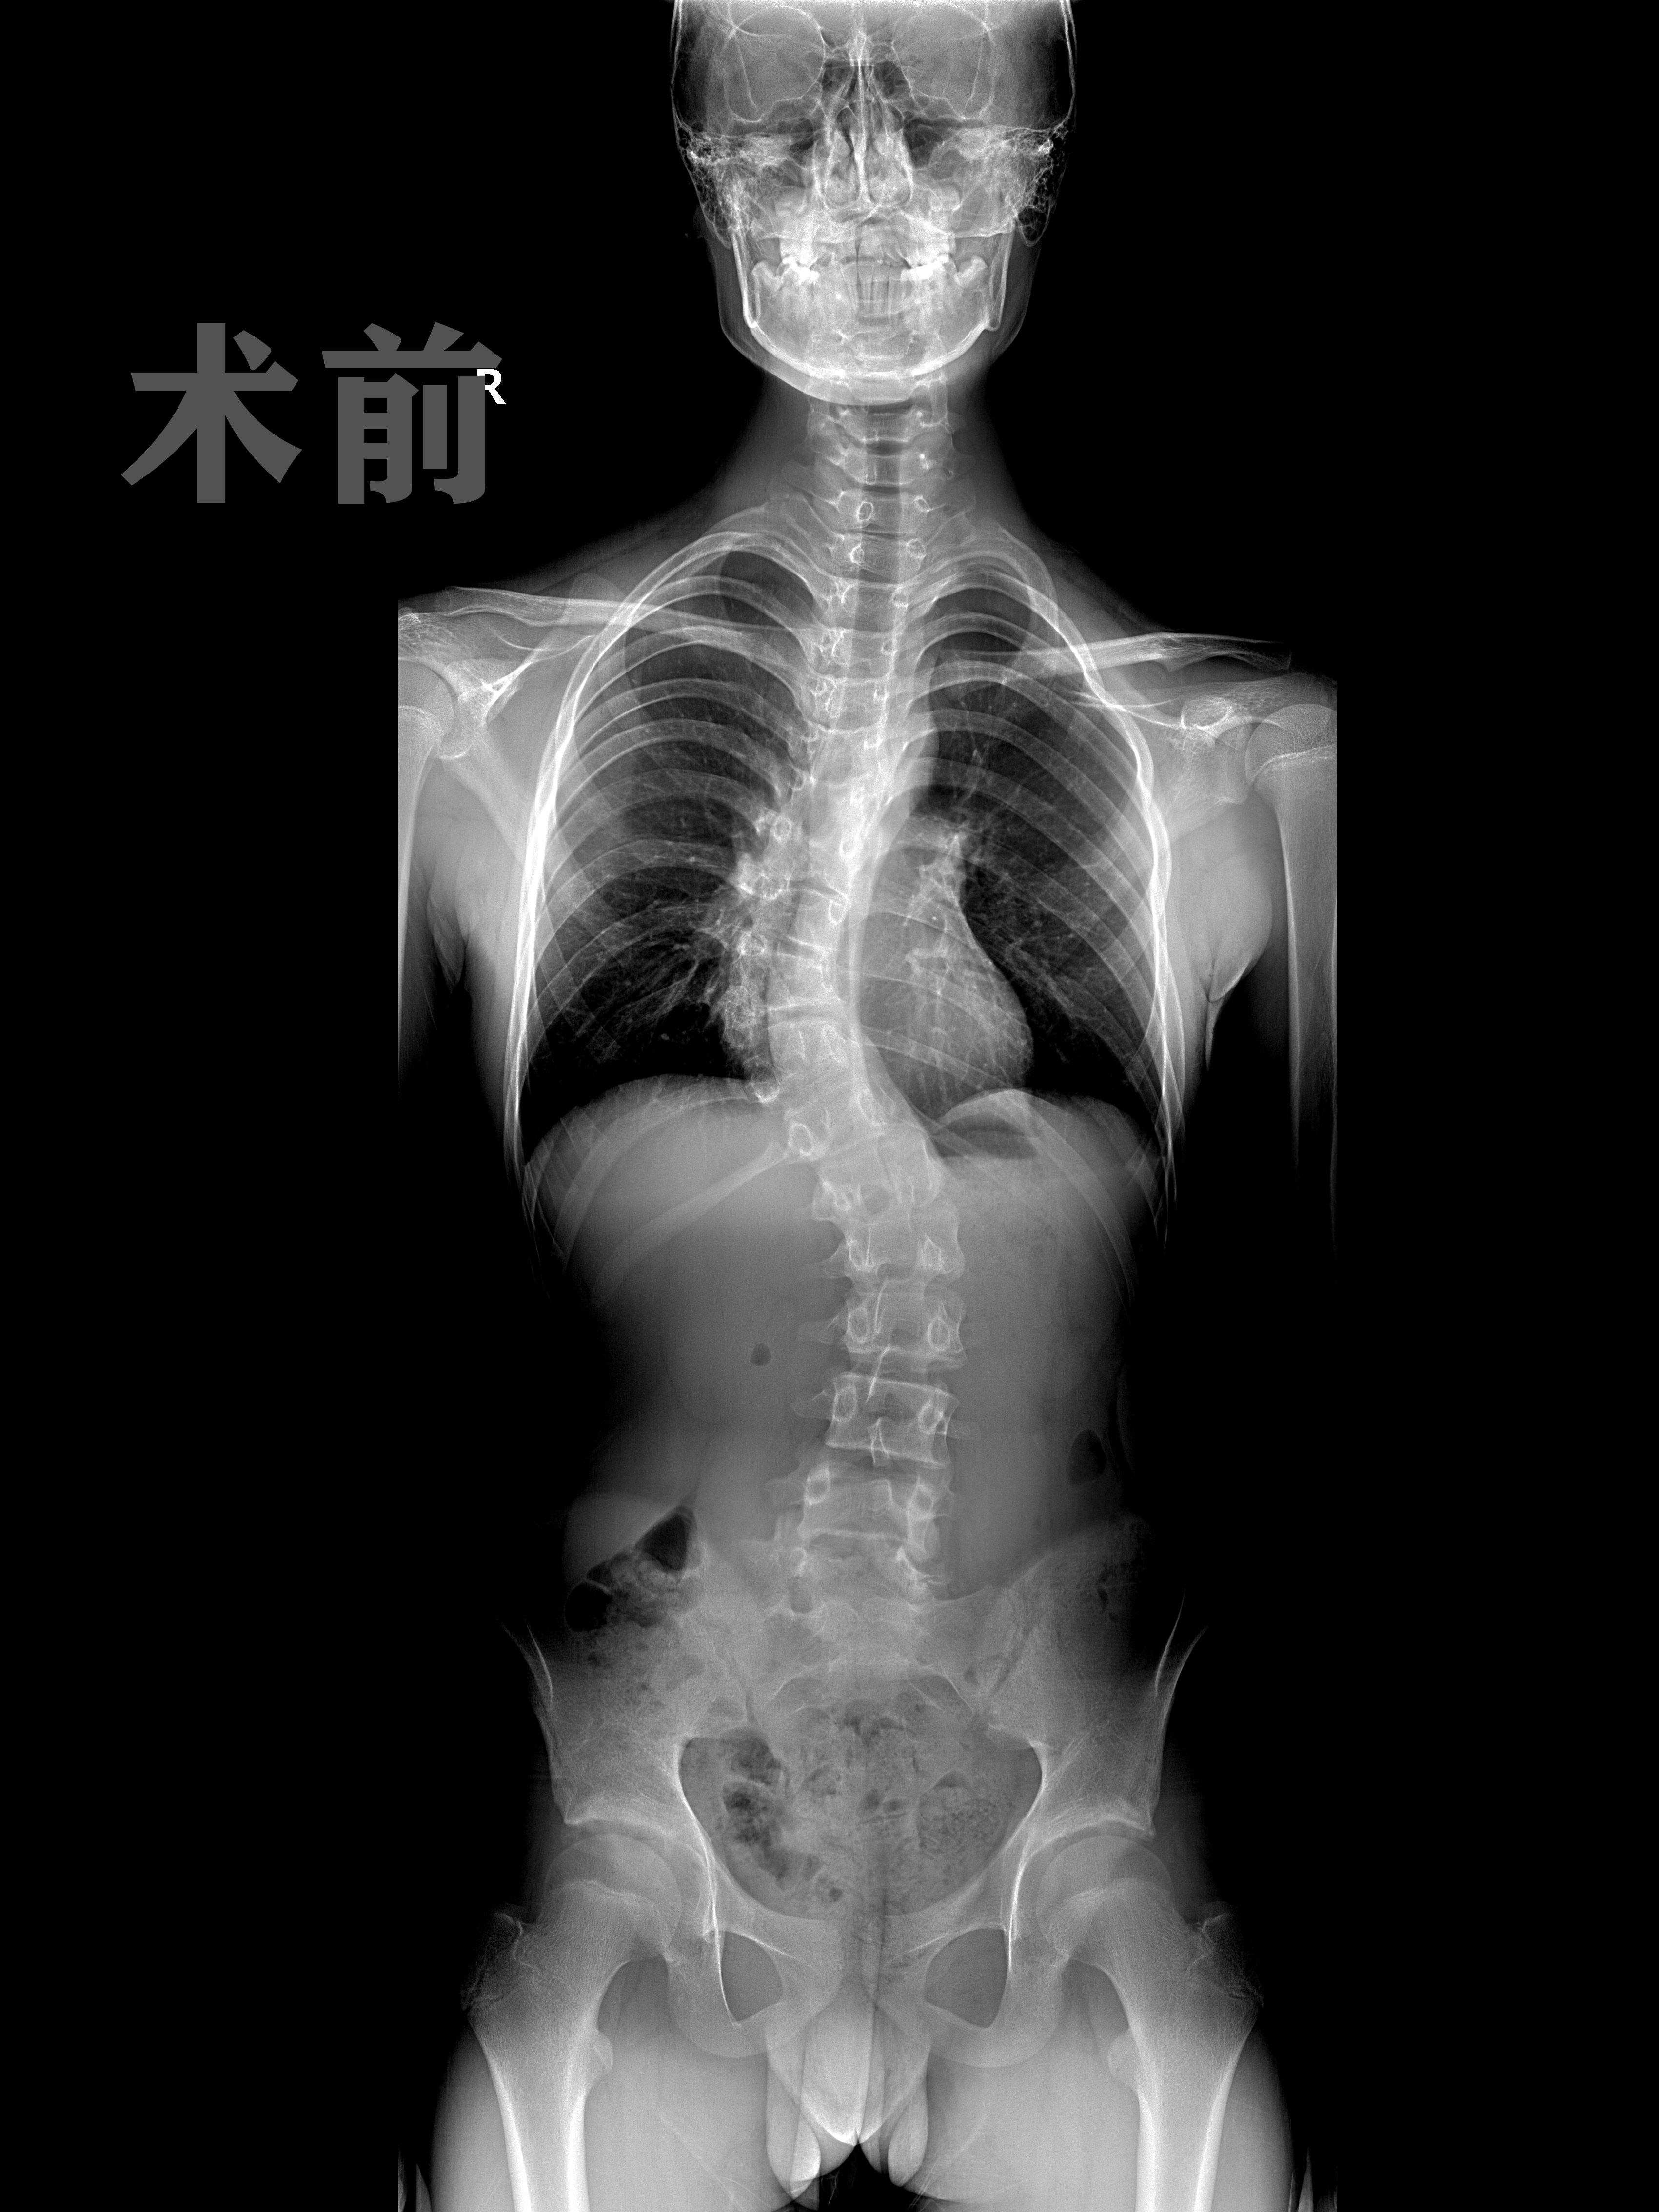

孩子脊柱侧弯会引起背部不对称,胸部也不对称。由于脊柱的侧凸,严重者可以引起胸背部或腰背部明显的不对称,并可有剃刀背和胸廓畸形。轻者可以通过前屈试验加以检查,该试验是诊断特发性脊柱侧凸的重要方法,受检查者站立,双手平齐向前弯腰,检查者在前方观察其背部两侧是否对称,如果有脊柱侧凸,则背部两侧不对称。

脊柱侧弯以后,会对患者的呼吸造成影响,严重的甚至会导致患者运动受限。因此患者可以到医院当中对脊柱进行检查。采用全脊椎四位片、CT检查以及三维重建的方式来进行检测,另外还可以通过X线的检查来查看脊柱是否有凸起或侧弯的情况。